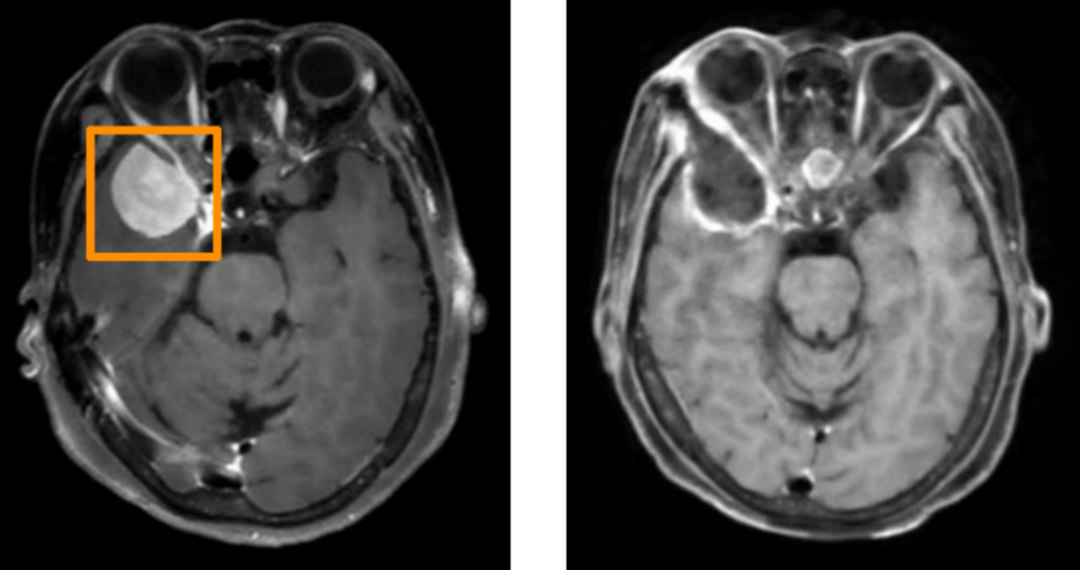

54岁的张女士(化名)因持续2个月的间歇性头痛就诊于省医神经外科。头颅CT检查显示其右侧颞叶巨大脑膜瘤,压迫邻近脑组织,直径达3厘米,如果得不到及时处理,患者可能会面临出现眼球运动障碍甚至失明的风险,手术治疗迫在眉睫。

左图为术前MRI,术后MRI(右图)显示肿瘤已全切除